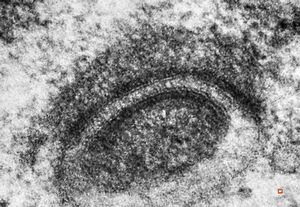

M,21y. | annulate lamellae - intracranial germinoma

M,21y. | annulate lamellae - intracranial germinoma